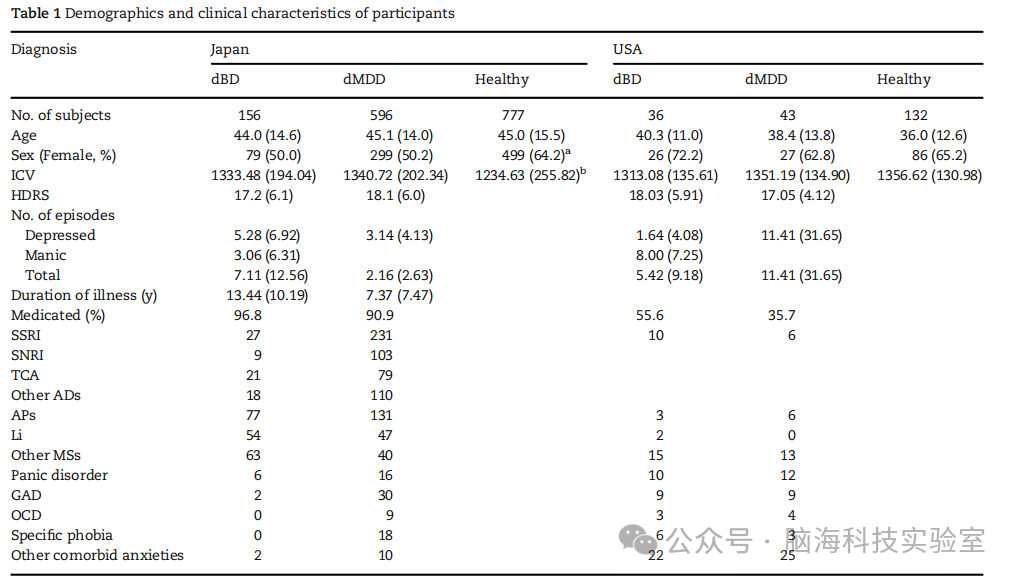

日本样本包括来自3所大学医院、2所精神科医院和1所神经科学研究所的596名单相抑郁患者、158名双相抑郁患者和777名健康参与者(表1)。参与者的详细信息总结在补充方法和补充表2中。在日本样本中,各组之间在性别分布、效应量和颅内体积上存在显著差异,但在年龄上没有显著差异、效应量相对较小。美国样本包括来自德克萨斯州圣安东尼奥一所大学医院的43名单相抑郁患者、36名双相抑郁患者和132名健康参与者(表1)。各组之间在性别分布、颅内体积和年龄上没有显著差异。本研究的所有参与者均为右利手。在日本样本中,汉密尔顿抑郁量表的平均得分为17.6(6.00)(n = 370),平均病程为9.18(8.71)年(n = 375),抑郁发作次数、躁狂发作次数和总发作次数的平均值分别为2.52(3.60)(n = 288)、3.00(8.81)(n = 48)和3.10(6.20)(n = 288)。这些指标仅在部分中心进行了收集,而在其他中心则通过临床评估了抑郁的严重程度。本研究获得了每个参与地点的机构审查委员会的批准,并在向参与者提供研究的完整描述后,获得了每位参与者的书面知情同意。

表1参与者的人口统计学和临床特征